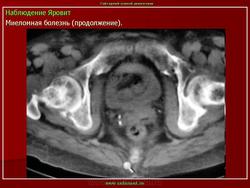

Миеломная болезнь